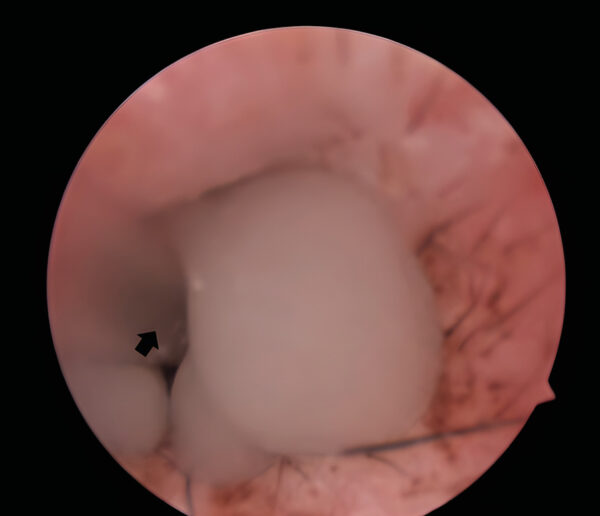

No obstante, en algunos pacientes con otitis media, la membrana timpánica puede mantenerse íntegra, aunque mostrando alteraciones tales como opacidad, cambios en la coloración (de blanco perlado a grisáceo), abombamiento o presencia de líquido (exudado purulento o mucoide) o formaciones carnosas (como pólipos o neoplasias) detrás de la membrana.

La videotoscopia permite la visualización directa de los pólipos inflamatorios, que suelen estar asociados a una secreción mucopurulenta abundante en el conducto auditivo externo. Por ello, el lavado de dicho conducto es fundamental para mejorar la visualización de estas masas carnosas y facilitar su diagnóstico.